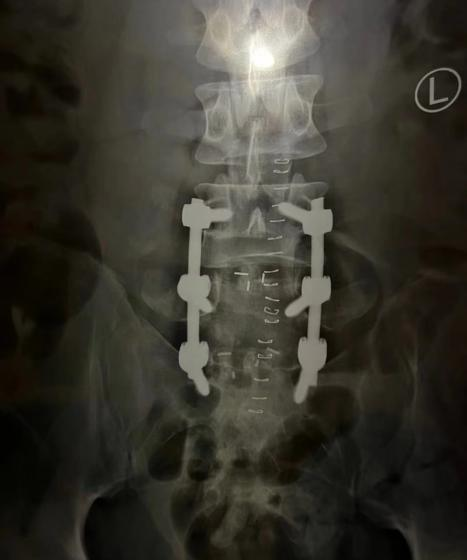

张宝丰花费4000多元购买了一个疗程的正骨服务,但“对方收款的二维码是属于一个烟酒店”。“当时我也没太在意,毕竟是朋友介绍的”,他告诉央视网《新闻+》记者,两次正骨主要是年长的医师指导两位年轻的徒弟操作,但是第二次正骨结束后,问题非但没有解决,反而更严重。原先只需要微创处理的腰椎间盘突出变成了腰椎滑脱、腰椎峡部裂,需要在后背开刀,打6根钉子固定脊柱。

打了6根钉子的脊柱/受访者供图

手术后的张宝丰在床上躺了3个月,“就像是废人一样,即便是在家里想简单扛个东西都不行,有时候还得我妈帮我”。事后,“心里很不是滋味”的张宝丰决定起诉,“好在我爱人当时在旁边拍了一些视频,捕捉到他在给我正骨,以及一些比较野蛮的动作”。通过这些关键证据,张宝丰在这场医疗损害案件中获得了胜诉,但他告诉央视网《新闻+》记者,“和手术、康复费用相比,没有赔偿多少钱”。